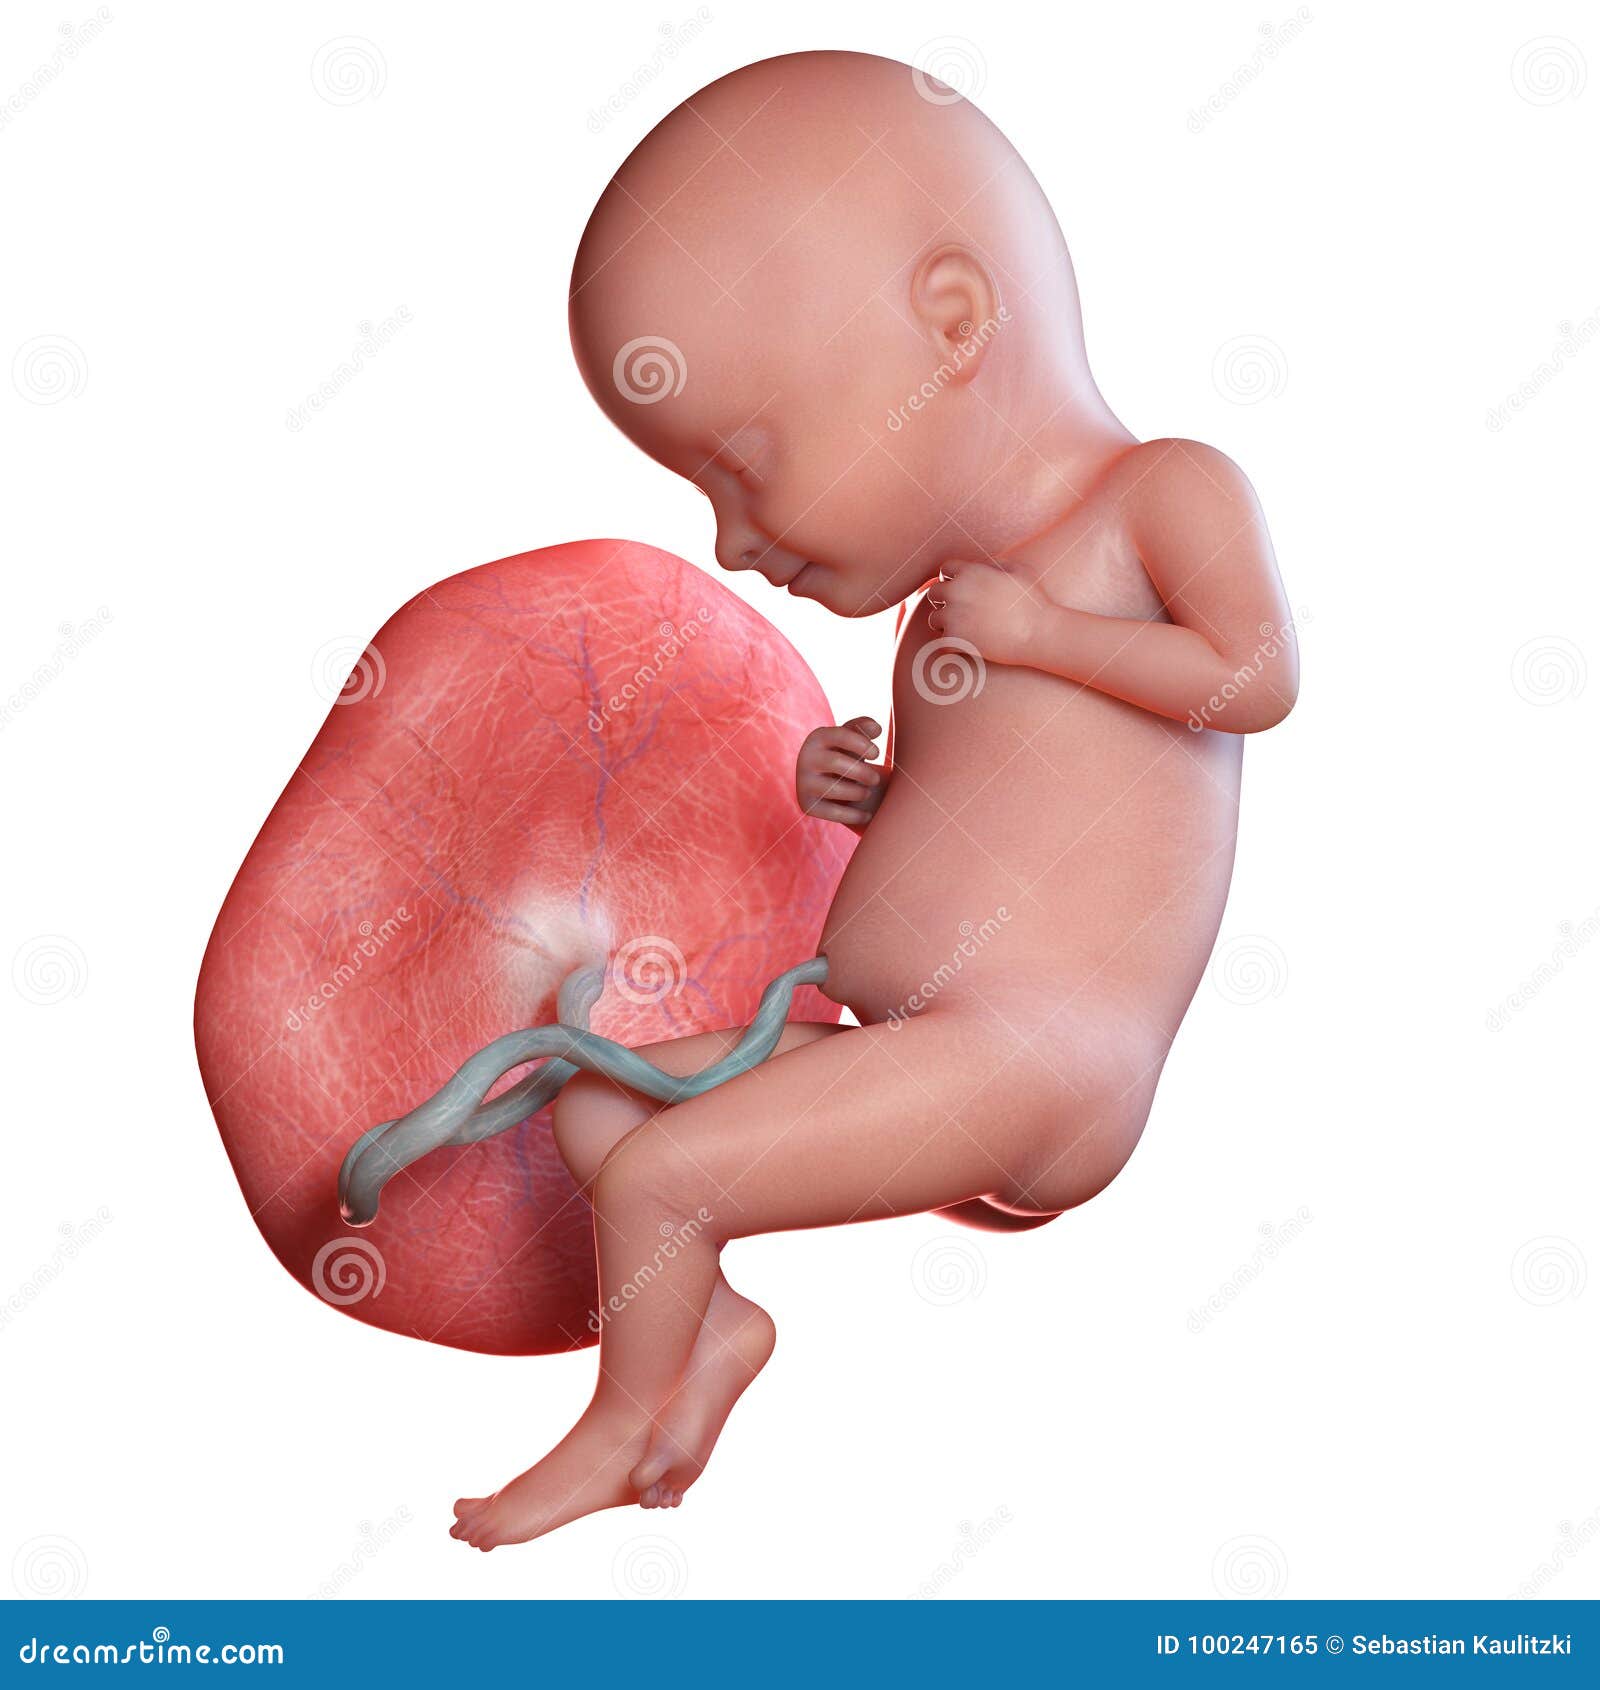

На восьмой неделе активно развивается плацента, что существенно влияет на способ питания малыша. Все необходимое для полноценного питания ребёночек будет теперь получать через пуповину. Невидимая нить, связующая мать и дитя, не прервётся и после рождения.

Плод все еще находится внутри амниотического мешка, и плацента продолжает развиваться, образуя структуры, которые помогают прикрепить плаценту к стенке матки.

На этой стадии плод все еще получает питание из желточного мешка.

Плод все еще находится в амниотическом мешке и получает питательные вещества из желточного мешка.Плацента развивается и прикрепляется к стенке матки структурами, называемыми ворсинками хориона.